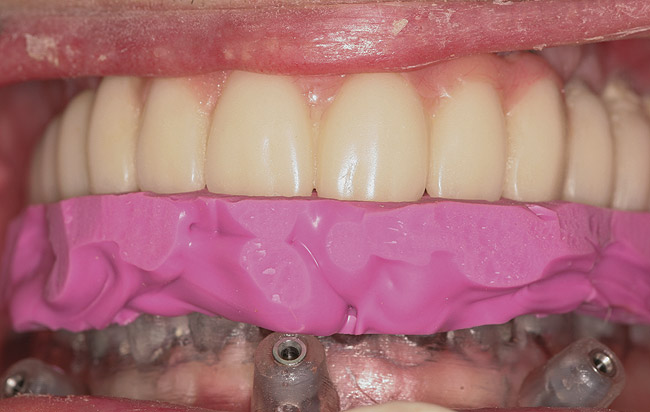

Figure 16  Laboratory-processed provisional restoration fabricated prior to surgery.

Figure 16

Figure 17  Provisional restoration placed at time of surgery.

Figure 17

Guided implant surgery involves reverse treatment planning. The ideal contour and arch position of the restoration is planned first, followed by virtual planning of the implant into that position according to the bony anatomy and clinical scenario. SLA surgical guides are then fabricated from the treatment plan. A dental laboratory next uses the SLA guide, with mounted casts, to fabricate provisional restorations prior to implant placement. At the time of surgery, the surgical guide is used to place the implants flaplessly, removing only a tissue core in the implant site(s). Abutments are immediately placed, and provisional restorations can be inserted.15-20 (Figure 12 through Figure 17).

Although technologies are available to place immediate definitive restorations, most clinicians are placing provisional restorations, for many reasons. Whether performed flaplessly or not, after surgery the final gingival contours and anatomy cannot be predicted. The clinician and dental technician can gain invaluable information as to the gingival contours and esthetics by observing tissue responses from the provisional restoration. Whether implant placement is guided or nonguided, a small number of implant failures occur. Most surgery-related failures take place within the first 3 to 4 months after implant placement. Surgical and restorative implant failure management is best accomplished prior to insertion of the definitive restoration. According to Abrahamsson et al, changing from a healing abutment to a permanent abutment did not result in a change in the dimension and quality of the transmucosal attachment that developed. It did not differ from the mucosal barrier that formed on a permanent abutment placed after surgery.31 An acrylic resin occlusal surface or a composite restoration reduces the forces of impact and has a better shock-absorbing behaviour compared to ceramic materials32; this is an additional reason for placing immediate acrylic resin provisional restorations, rather than immediate definitive porcelain restorations.